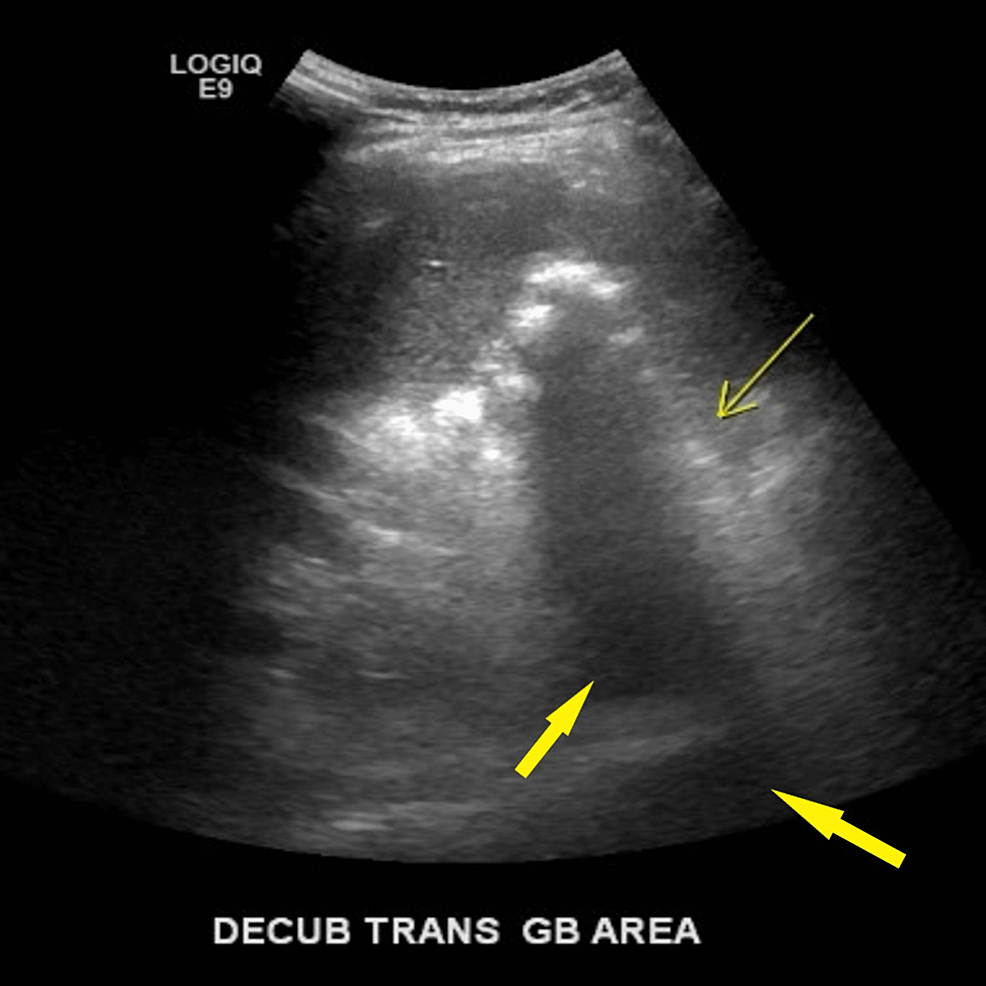

From www.researchgate.net

F, 74 yo with the diagnosis of IEP. Patient with 8x increase of lipase Lipase No Gallbladder These might contain amylase, lipase and protease. By including lipase in your. What happens when you don’t have a gallbladder? Lipase supplements are specifically designed to support the digestion of fats, making them an excellent choice for individuals without a. Symptoms like sticky or floating stool, digestive upset after meals, even dry skin and hair loss can signal that you’re. Lipase No Gallbladder.